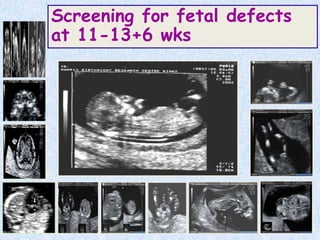

Screening for fetal defects

at 11-13+6 wks